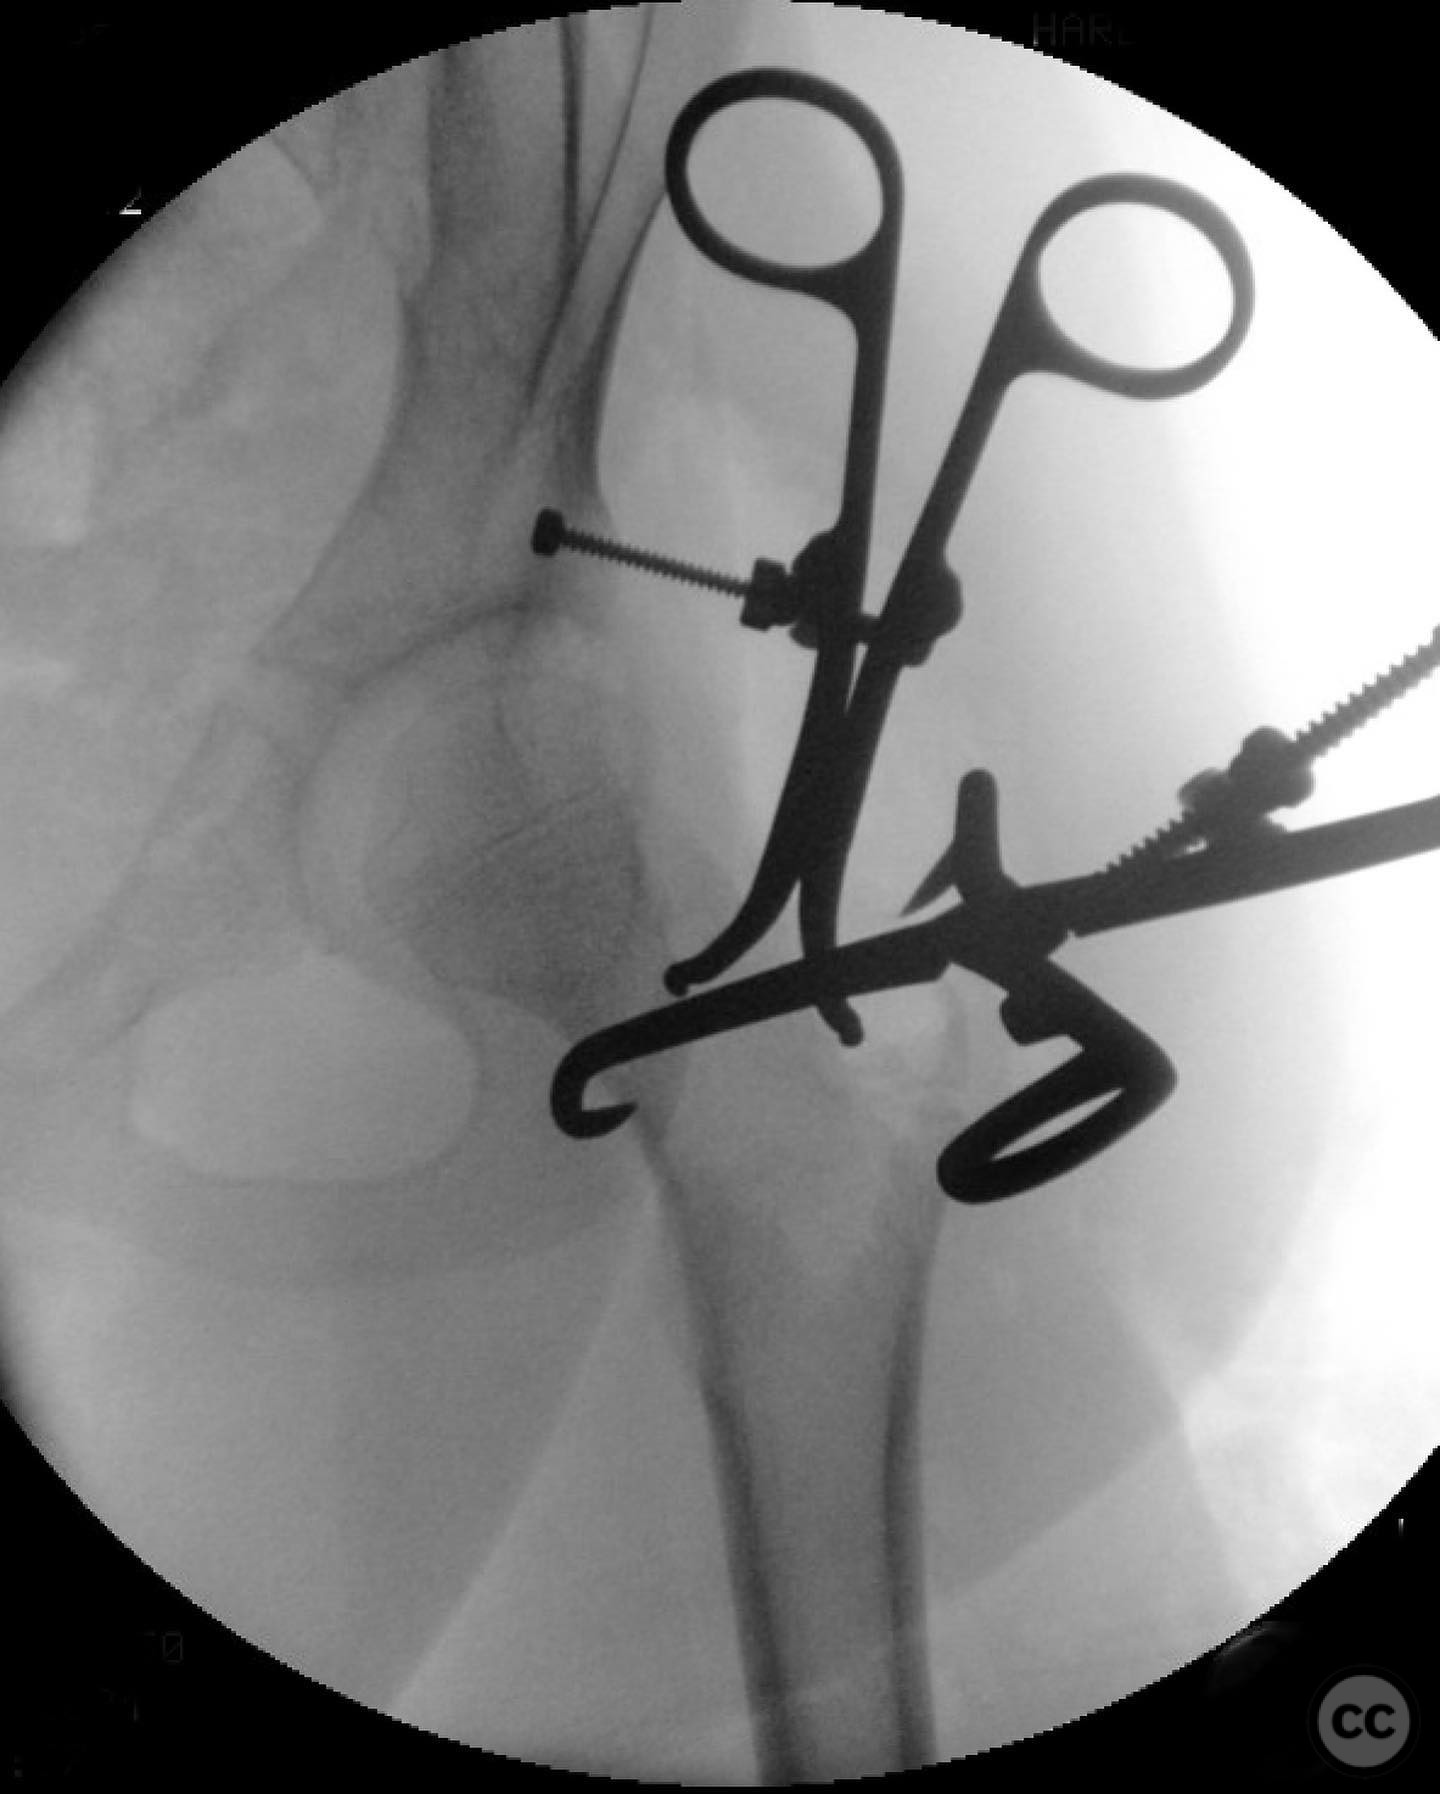

Clinical and radiological findings:  An 8-year-old boy fell approximately 15 feet from a treehouse, sustaining a displaced femoral neck fracture. There were no associated injuries to the head, spine, chest, or abdomen. The initial radiological assessment confirmed a displaced fracture of the femoral neck. Neurovascular examination was unremarkable.

Anatomical surgical approach:  A modified Smith-Petersen approach was utilized, involving an incision along the anterior aspect of the hip, allowing for direct visualization of the femoral neck. Subperiosteal dissection was performed to expose the fracture site without compromising the surrounding musculature. A separate lateral approach was employed for the application of fixation devices.

Operative remarks:

The surgeon emphasized the importance of achieving a high-quality reduction and stable fixation due to the displacement pattern of the fracture. A meticulous surgical approach was critical to avoid malreduction, which is not well-tolerated in pediatric patients. The modified Smith-Petersen approach provided excellent visualization for anatomic reduction, minimizing soft tissue damage.